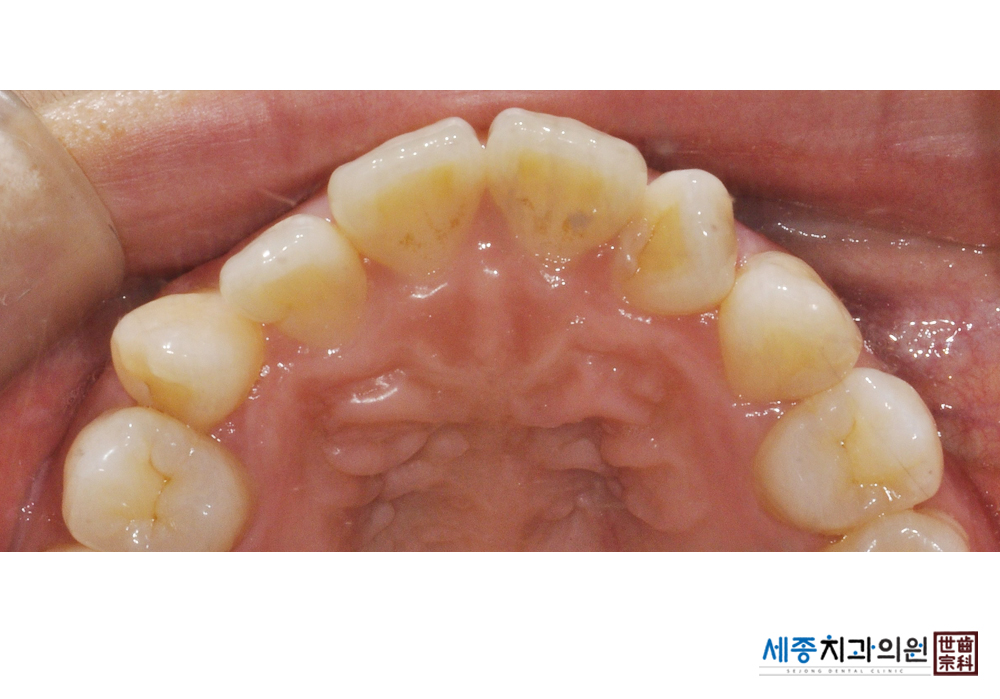

[스케일링] 치주질환 예방 스케일링

치료전 : 2020-01-27

치료후 : 2020-01-27

가글마취&저주파 스켈러를 사용한 스케일링